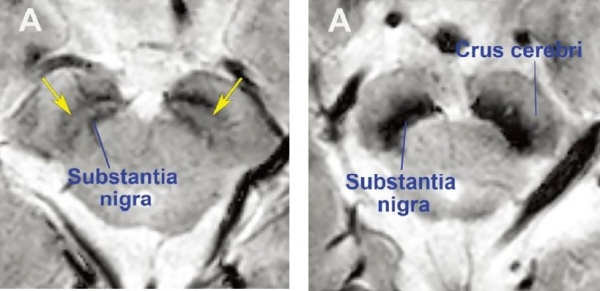

파킨슨병 진단을 위해서는 다양한 MRI 기술을 결합해 흑질 구조의 변화를 시각화하는 것이 중요하다. 과거 MRI로는 흑질 구조를 상세하게 보기 어려웠으나, 최근 보편화 된 3T 및 7T를 이용한 고해상도 MRI로 보다 자세히 촘촘하게 촬영이 가능해졌다.

파킨슨병의 병소인 나이그로좀(nigrosome) 영역의 음영을 이러한 고해상도 MRI를 통해 가시화하고 손상 부위를 파악함으로써 파킨슨병을 정밀하게 진단하는 것이다. (※ T(테슬라)는 MRI 촬영에 쓰는 자석 자장 세기로, 숫자가 높을수록 선명한 영상을 얻는다)

정상 모양의 흑질(좌), 파킨슨병 환자의 흑질(우) MRI 영상. 흑질의 검정 부위 사이에 좌측 그림의 노란색 화살표에 밝은 부분이 있으면, 정상, 우측 검정색으로 메워지면 도파민신경세포가 소실된 환자.)